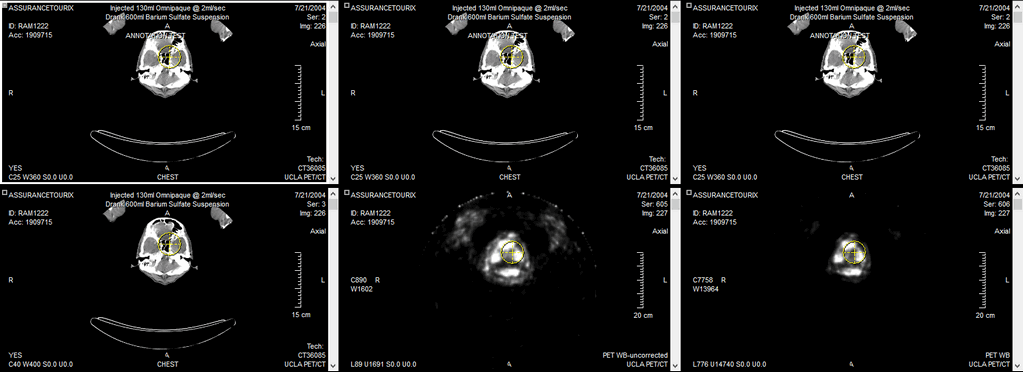

There are four Image View boxes visible on the screen above. In the event that a suspected area has been found and the user wants to view every image in the study that contains a view of it, clicking the area brings up every single possible view of that point. In the example below, this translates to a total of six images being displayed on the screen for that specific point.

Clicking any point on any of these images brings up all available views of the new location. The cursor can be dragged around in the image, and the Cross-hair pointer in all views are updated in real time.